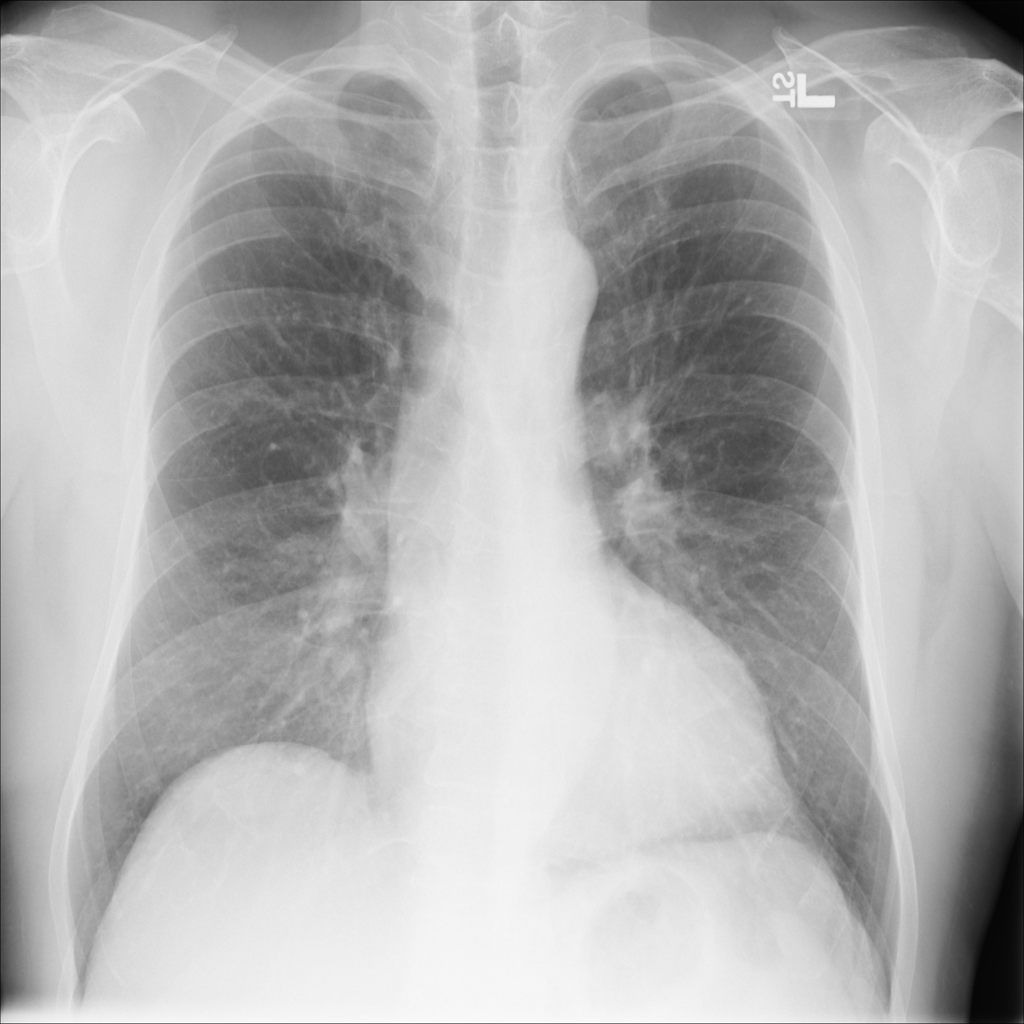

Cardiomegaly

Cardiomegaly means the heart appears enlarged on the chest X-ray. It is a descriptive imaging finding that can be related to heart strain, chronic pressure or volume changes, or even projection effects.

Showing up to 90 reference images for Cardiomegaly.

PAT-F3E7 · IMG-000Cardiomegaly

PAT-F3E7 · IMG-000

PA